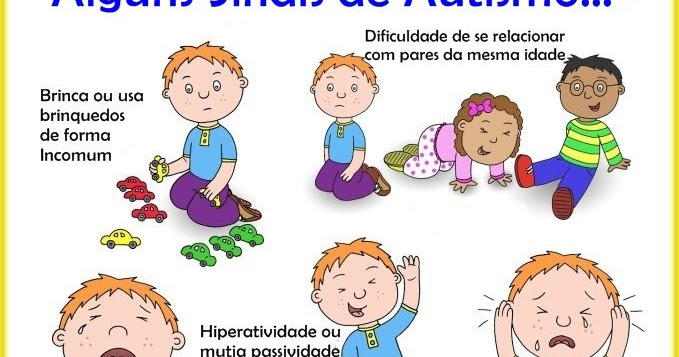

Alguns sintomas do Autismo - Psicologa Angra Luchi

Dia Mundial do Orgulho Autista: conheça os diferentes sinais da condição04 abril 2025

Dia Mundial do Orgulho Autista: conheça os diferentes sinais da condição04 abril 2025 -

Sintomas de autismo04 abril 2025

Sintomas de autismo04 abril 2025 -